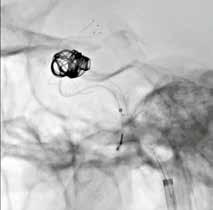

Wenn Neuroradiologen beispielsweise intrakranielle Aneurysmen mit dem endovaskulären Coiling-Verfahren behandeln, benötigen sie Sichtkontakt zur Läsion. Je besser sie die feinen, über einen Mikrokatheter in das Aneurysma vorgeschobenen Platinspiralen, die sogenannten Coils, sehen, desto präziser

HD-Flachdetektor

und zügiger können sie diese im Aneurysma packen und dessen Innenwand abdecken. Häufig muss die entfaltete Platinspirale zusätzlich noch durch einen Stent mit sehr feinem Drahtgeflecht gestützt werden, der ebenfalls genau zu platzieren ist.

Durch die Vergrößerungsmöglichkeit im HD-Modus können diese kleinen

Devices und Gefäßstrukturen auf dem Monitor klar dargestellt werden. Somit ist auch der Behandlungsfortschritt genauer nachvollziehbar. Der HDFlachdetektor funktioniert in diesem Zusammenhang wie ein Mikroskop für den Neuroradiologen. Es leuchtet ein, dass die HD-Technologie daher zu besseren Behandlungsergebnissen und höheren Überlebensraten führt.

Klinischer Fall: 11 mm Kavernöses Karotisaneurysma rechts; Behandlung mit LVIS-Blue-Stent und Coils; Bildgebung mit lateralem HD-Flachdetektor, 6 cm x 6 cm FOV, Fluoro-Modus.

Bildgebung mit Standard- und HD-Flachdetektor.